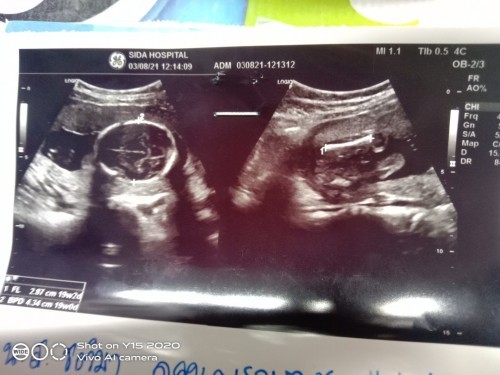

พึ่งอัลตราซาวมาวันนี้คะ อยากรู้ว่าเป็นส่วนไหนของน้อง ☺️☺️(คุณหมอบอกว่าอาจจะเป็นผู้หญิง)

รูปแรกส่วนหัวค่ะ รูปสองเป็นหว่างขาน้องหนีบเห็นไม่ชัดเลยค่ะ